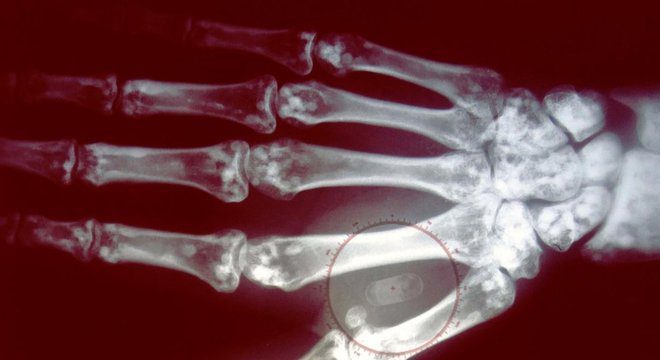

Os microchips têm o tamanho de um grão de arroz

BBC

O microchip é implantado debaixo da pele, entre o polegar e o indicador

Seu tamanho é minúsculo, mas pode conter muitas informações

Paul Hughes